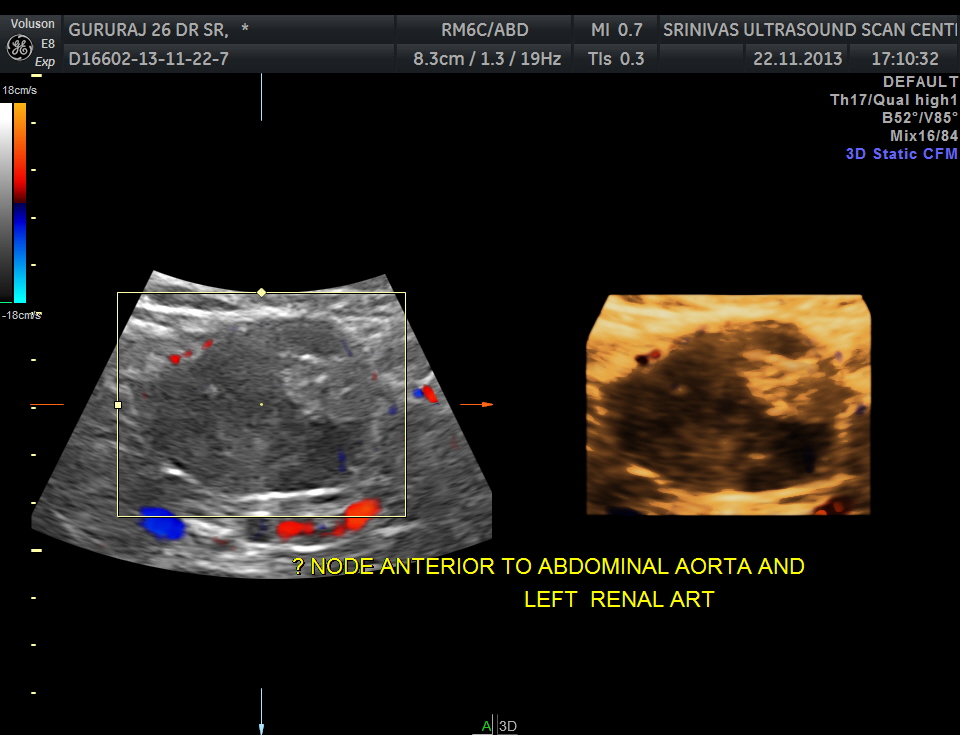

The following image was obtained with the transducer in the mid epigastric region and an inch to the left of the mid line.

This mass visualised there . This was antero-lateral to the aorta and showed mixed echotexture , with some vascularity.

This was not mobile and all i could offer was a description of what was seen with the impression of a mass of unknown origin – ?? enlarged node and advised further work up.

He underwent a contrast CT and was found to have a mass arising from the intestinal wall. He underwent surgery subsequently and the mass was removed . It was a benign leiomyoma arising from the jejunal wall and showed some erosions on the inner aspect ( cause for the anemia ) . Now came the pleasant surprise for everybody.His anemia improved and his headaches disappeared totally. The explanation offered was reactive thrombocytosis due to the anemia probably caused the hemicranial pain and when that was taken care of he was better.